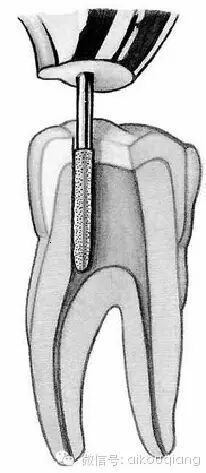

4、有时可以去除部分牙本质领(见下图),但我认为这个地方还是用金刚砂钻针比较好,要是有安车针就更好了,因为不小心的话有牛人一定会给你修整出“啤酒桶样”的破坏。

口腔H锉怎么消毒根管治疗器械的选择_https://www.jmylbn.com_新闻资讯_第9张

图 牙本质领

口腔H锉怎么消毒根管治疗器械的选择_https://www.jmylbn.com_新闻资讯_第10张

图 金刚砂钻针修整牙本质领